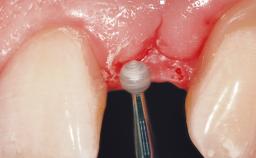

Soft Tissue Grafting Simultaneous

Soft Tissue Anatomy Intact Defective

Soft Tissue Contour and Volume Slightly compromised